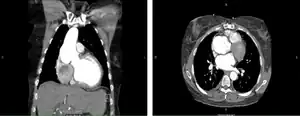

CT of the chest. Coronal (left) and axial (right) views demonstrating pathologic dilatation of the aortic root and ascending aorta. On the axial image, a dissection plane is noted in the aortic root.

Degeneration of pulmonary autograft and aortic dissection extending into the non-coronary sinus.